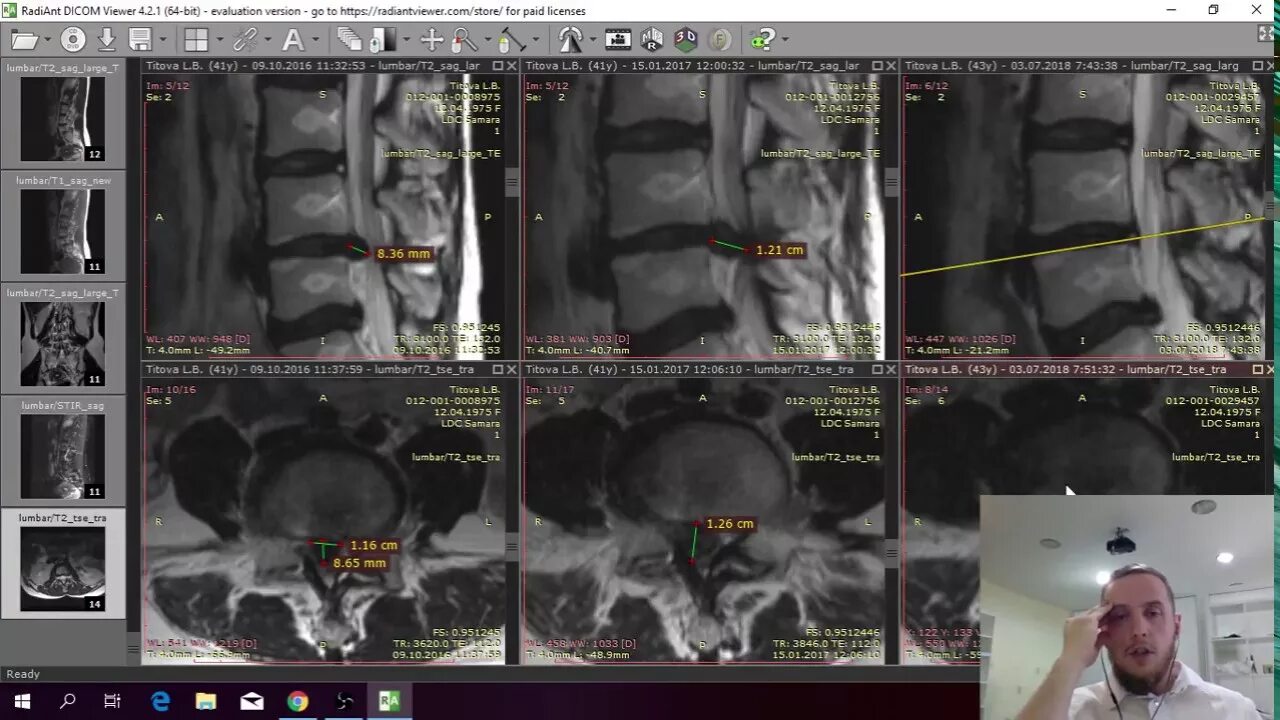

Резорбция епифанов